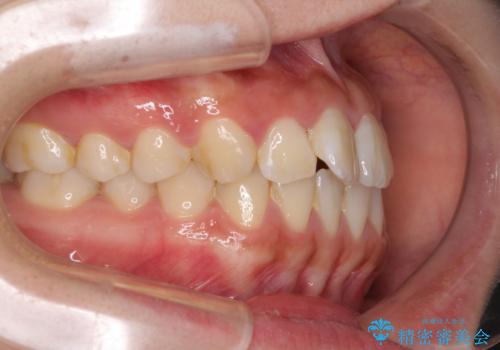

軽微な歯列不正をワイヤー矯正で整える

- 上顎歯列と下顎前歯の叢生を気にして来院された患者様です。

上顎からワイヤー矯正を開始し、終了間際から下顎前歯の叢生解消するよう計画しました。

部分矯正でしたが、咬み合わせに違和感が出ることなく気になる部分を改善させることができました。